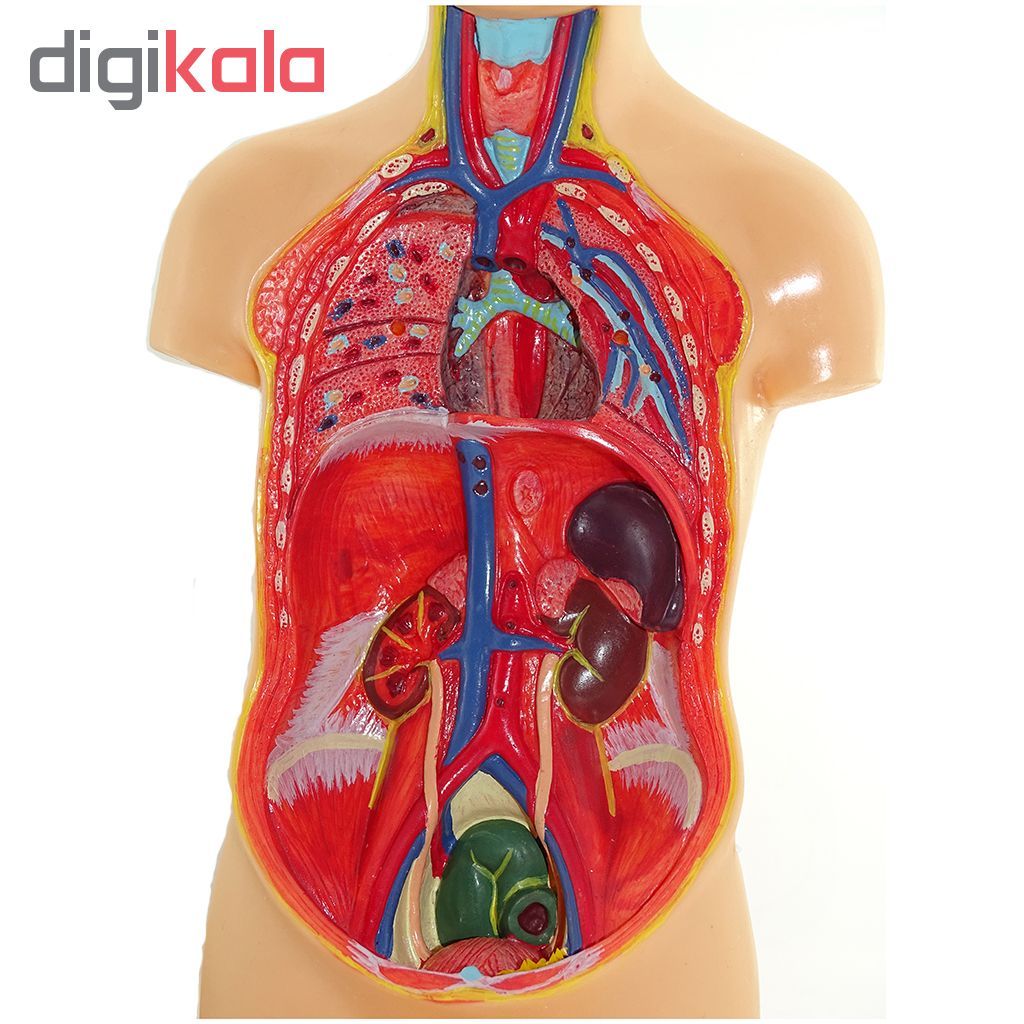

عکس اسکلت بدن انسان با کیفیت. عکس اسکلت عکس اسکلت برای پروفایل عکس اسکلت انسان عکس اسکلت خفن عکس اسکلت بدن انسان با کیفیت عکس اسکلت بدن انسان عکس اسکلت ترسناک عکس اسکلت فانتزی عکس اسکلت فانتزی دخترانه پرچم عکس اسکلت. عکس با کیفیت اسکلت داخلی انسان و درد و گرفتگی در ناحیه استخوان زانو ویژه استفاده در امور تبلیغاتی و تجاری طراحی کاتالوگ بروشور و تراکت با موضوع پزشکی فیزیوتراپی ارتوپد دکتر روماتیسم فیریوتراپ طب فیزیکی. عکس اسکلت بدن انسان زن و مرد آناتومی ساتین 16 سپتامبر 2017. اسکلت داربست بدن است تمام قسمت های بدن روی اسکلت قرارگرفته اند بدن انسان از ۲۰۶ قطعه استخوان تشکیل شده است این استخوان ها طوری با نظم کنار هم قرار گرفته اند که انسان را قادر می سازد حرکات دقیقی داشته باشد.

اسکلت جمجمه و گردن انسان ستون فقرات آناتومی اسکلت جمجمه و گردن انسان ستون فقرات آناتومی تصویر با کیفیت را از لینک زیر می توانید دانلود کنید. ۱ مطلب با کلمه ی کلیدی عکس اسکلت بدن انسان با کیفیت ثبت شده است گالری نسیم جدید ترین و با کیفیت ترین عکس های مناسبتی. عکس با کیفیت آناتومی اسکلت بدن انسان و درد و دیسک در قسمت مهره های ستون فقرات کمر ویژه استفاده در امور تبلیغاتی و تجاری طراحی کاتالوگ بروشور و تراکت با موضوع بیمارستان ها و کلینیک ها و درمانگاه ها و مطب ها پزشکان و.